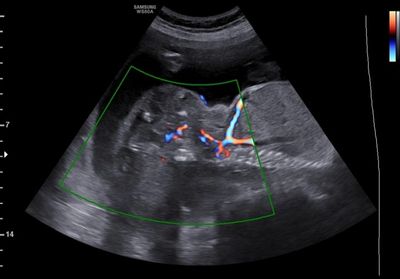

Large Sacrococcygeal teratoma with vascularity